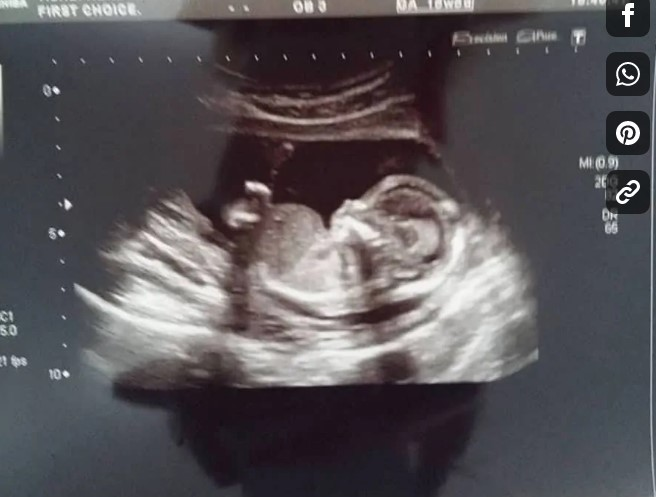

然し、妊娠4か月目の頃、愛犬ケオラは、アルハンナの大きくなってきたお腹を引っ掻いたり、お腹に向かって訳もなく呻き始めたりと、奇妙な振る舞いをするようになった。

アルハンナの大きくなったお腹に、ケオラは呻き声を上げ、何時間にも渡ってアルハンナの大きなお腹を引っ掻き始めるようになった。まるでケオラは何かを見せようとしているかのように、鼻をアルハンナの胃の部分に突き刺そうとするような仕草を見せた。

アルハンナは激しい腰痛の症状は続いているけど、妊娠自体に影響は及んでおらず、赤ちゃん共に心身健康であると、彼女の医者が告げた内容を報告し、… またアルハンナは、ここ数週間の間に、ケオラが奇妙な行動を見せている事も書いた。

愛犬ケオラは、大きくなったお腹を抱えるアルハンナに対して、どうして奇妙な反応をしていたのだろうか?一

体何を伝えようとしていたのでしょうか?